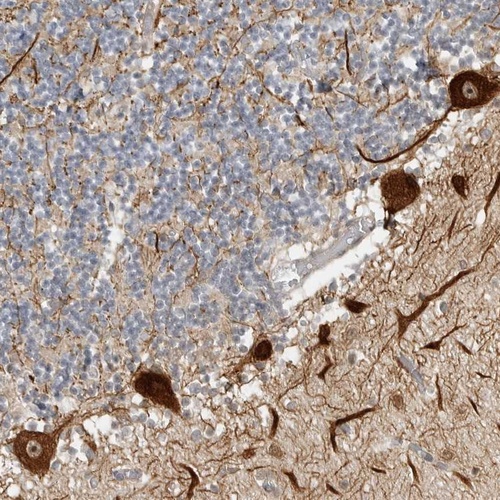

Immunohistochemical staining of human cerebellum shows strong dot like nucleolar and cytoplasmic positivity in purkinje cells.